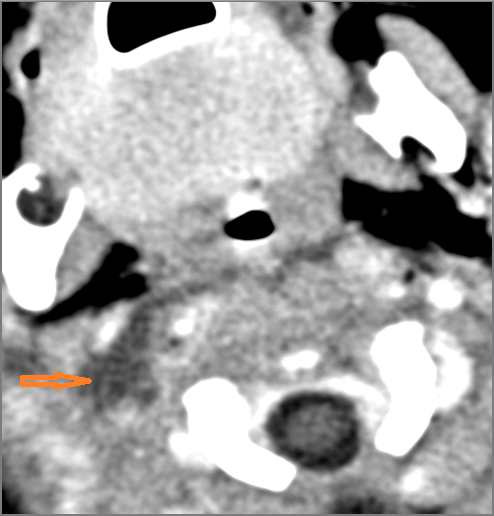

Other Cervical Lymph Nodes

Vascular Findings